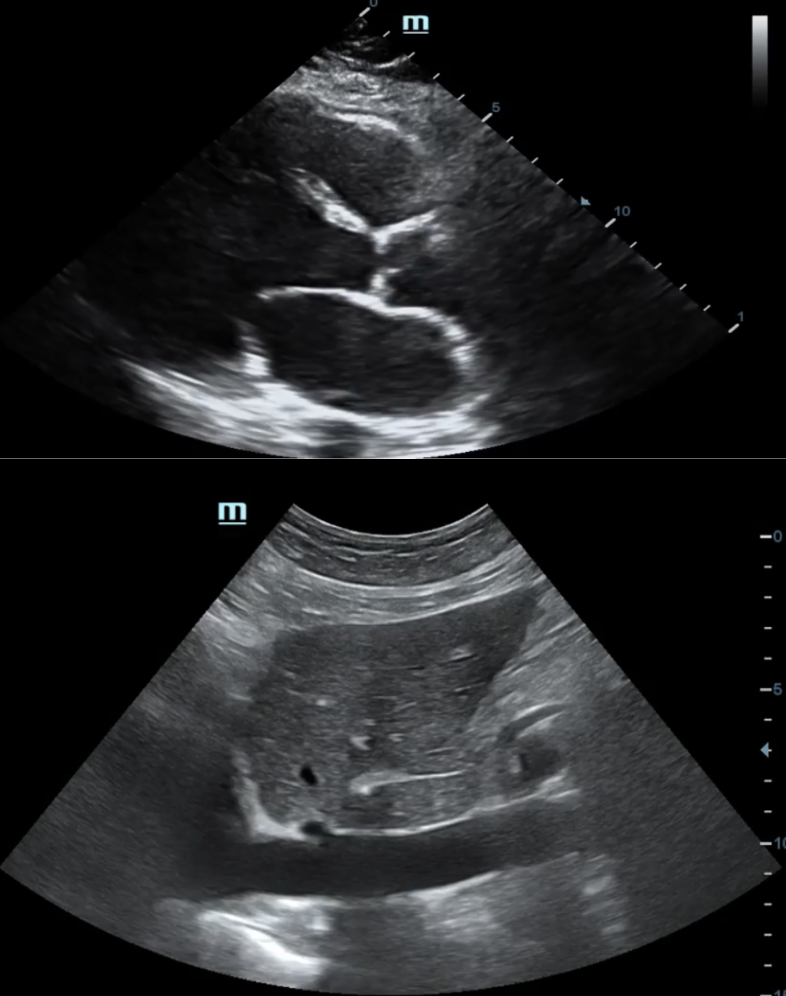

A nivel cardiológico, observamos una disminución de la fracción de eyección y un aumento de la presión venosa central.